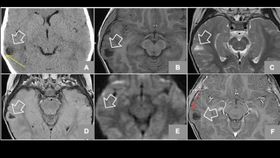

The rest of this article is behind a paywall. Please sign in or subscribe to access the full content.After imaging her brain using CT, PET, and MRI scans, Liders Burgos and colleagues were able to diagnose the cause of the girl’s gelastic (or laughing) seizures: They discovered a hamartoma -- a small, benign, tumor-like growth -- pressing on the temporal lobe of her brain.

Gelastic seizure was first described in 1877, and it comes from the Greek word “gelos,” for laughs. Normal laughter is an emotional reflex and its accompanying motor action involves the hypothalamus, the temporal cortex, and several regions of the brain stem. Gelastic nervous breakdowns occur mostly in the temporal lobe, and the rare condition is more frequently diagnosed in children.

Image: Burgos Zuleta et al., ecancermedicalscience 2014